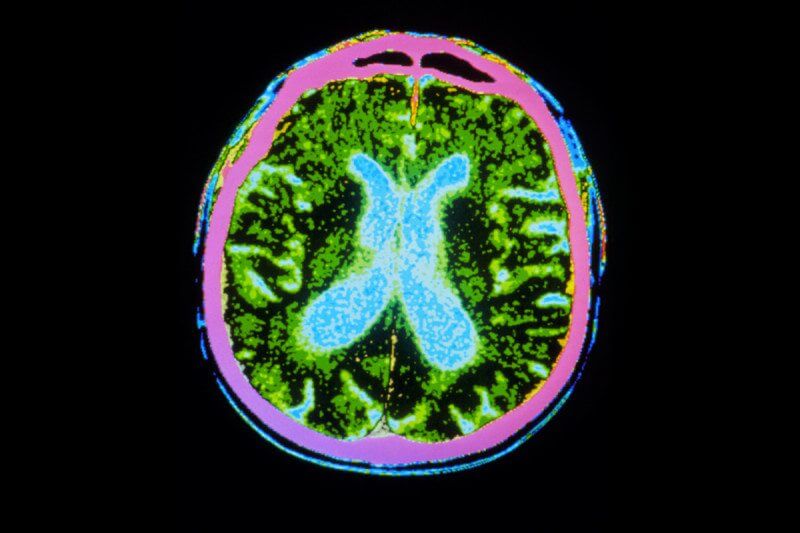

Как известно, болезнь Паркинсона развивается вследствие того, что клетки головного мозга, называемые астроцитами, перестают вырабатывать такое соединение, как дофамин. «Перепрограммирование» заключается в том, что полезный вирус, проникая в клетки человеческого головного мозга, заставляет их вновь производить полезный дофамин.

Исследовательская группа, возглавляемая доктором Эрнестом Аренасом, в ходе клинических испытаний ввела в мозг подопытных мышей, дофаминовые нейроны которых были разрушены, специальный вирус, который нес в себе четыре гена. Именно эти гены и отвечают за выработку гормона. Через 5 недель после «заражения» эксперты заметили, что мыши стали более активными, их походка улучшилась, а движения стали более четкими. В контрольной группе, которая не получала никакого лечения, изменений не наблюдалось.

При этом астроциты «инфицированных» мышей превратились, по сути своей, в дофаминовые нейроны, но только в месте инъекции. Близлежащие структуры остались неизмененными. Но и это еще не все. В рамках этого же эксперимента астроциты человека, но «в пробирке», были успешно модифицированы похожим образом, что говорит о достаточно высоком проценте успеха эксперимента. На данный момент ученые готовятся к последующим этапам клинических испытаний.